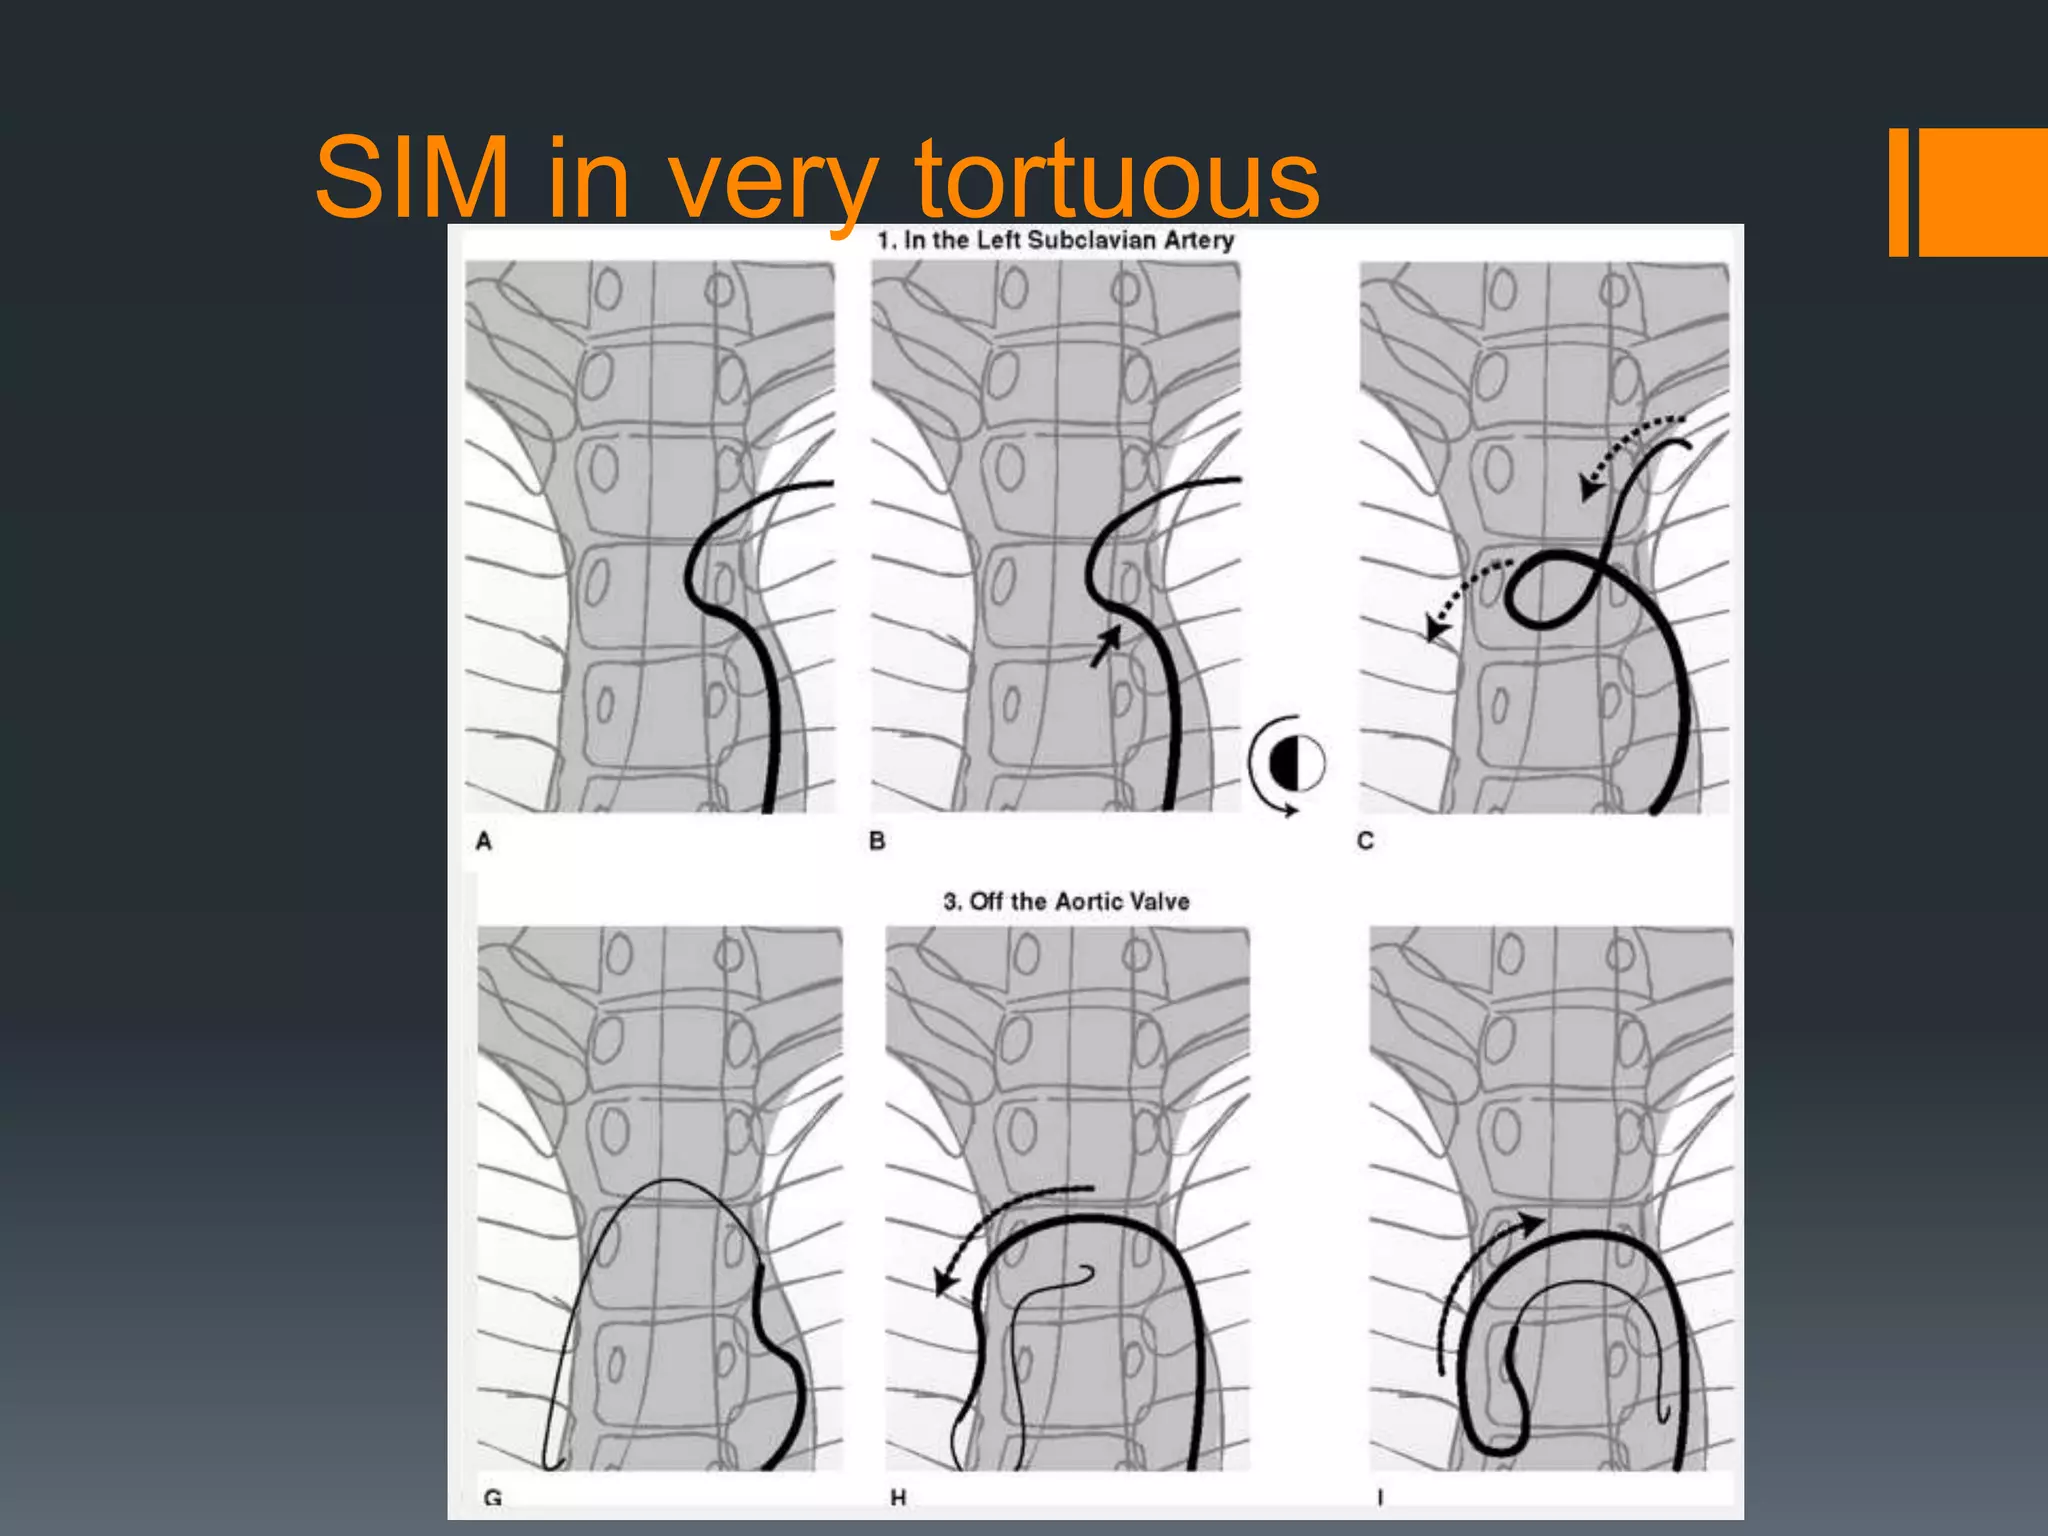

This document discusses tricks and techniques for difficult cannulations during neurointerventional procedures. It outlines strategies for accessing the aortic arch, internal carotid artery (ICA), and areas distal to aneurysms. Long sheaths, distal access catheters, and co-axial techniques are presented as options that have improved cannulation success. Guidance on sheath and catheter selection is provided for different vessel paths. The importance of catheter placement as high as possible in the ICA is emphasized. Reverse curve cannulations are also mentioned. Overall, the document stresses that careful cannulation is critical for procedural success and different strategies may be needed depending on the vessel target.